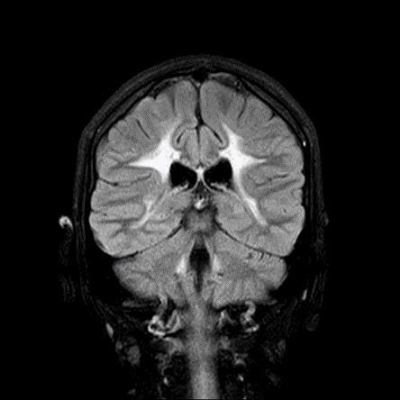

- A) Aksiyel T2A ve koronal T2A sekanslarda sentrum semiovale, korona radiata ve bazal ganglionlar düzeyinde bilateral frontoparietal derin periventriküler beyaz cevherde birleşme eğilimi gösteren hiperintens gliotik sinyal değişiklikleri (oklar) ve aksiyel T2A serilerde servikal spinal kordda posterior kolonda, lateral kesimlerde sinyal artımları (oklar) izlendi.

- LBSL, karakteristik radyolojik özelliklere sahiptir. MRG’de tipik olarak bilateral ve simetrik beyaz cevher sinyal değişiklikleri görülürken, subkortikal U lifleri, internal kapsülün posterior kolları, trigeminal sinir traktları, serebellum, korpus kallozumun spleniumu, medulla oblongata ve omurilikteki dorsal kolonlar ile lateral kortikospinal traktlar genellikle korunur.

- Etkilenen bölgelerde T1’de hipointens, T2/FLAIR’da hiperintens sinyal değişiklikleri izlenir. DWI’de lezyonların periferinde kısıtlı difüzyon görülebilir. MRS’de beyaz cevherde laktat artışı saptanabilir, ancak bu her hastada mevcut değildir.